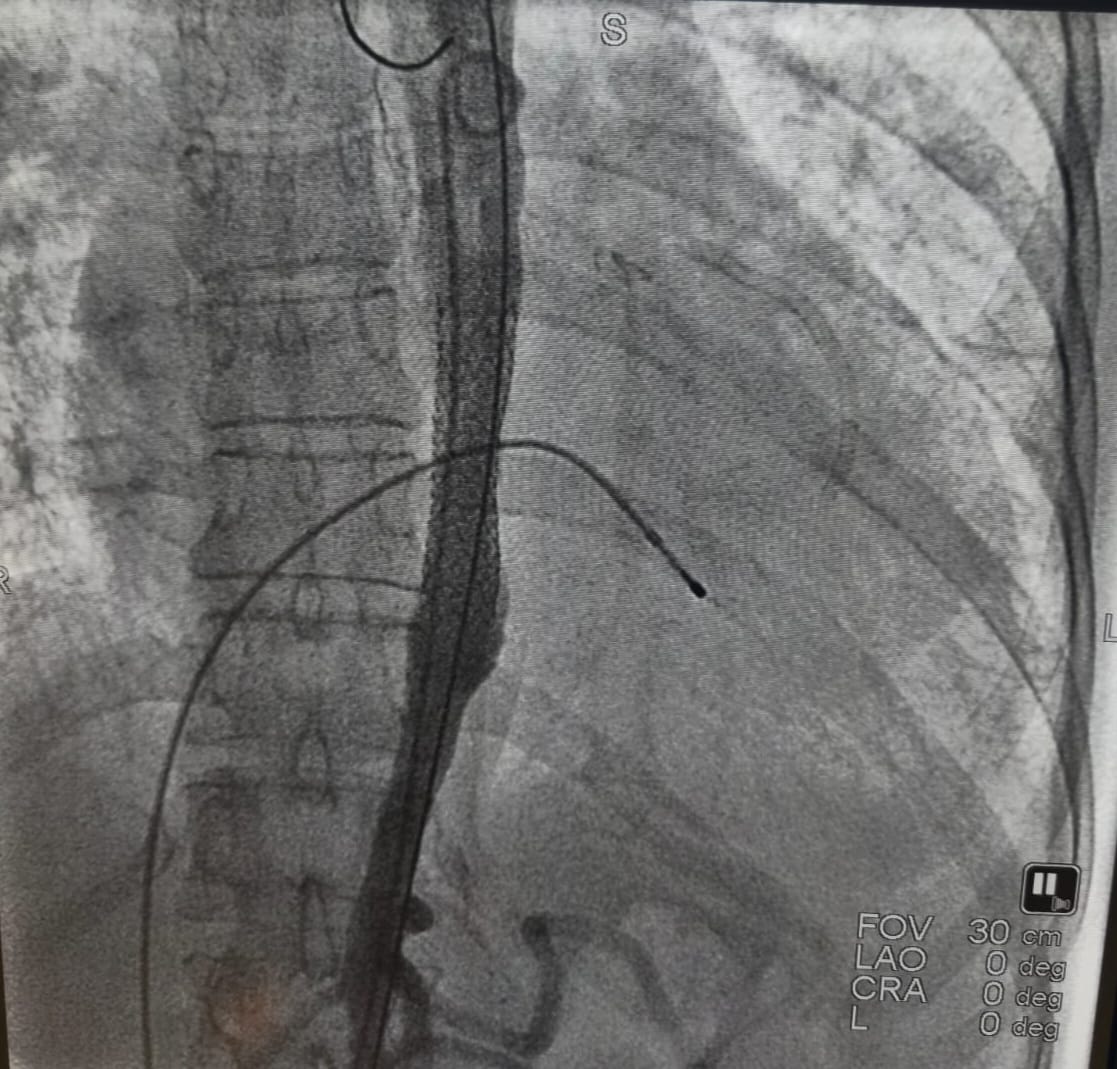

Acil servise başvurmasının ardından hızla anjiyografi ünitesine alınan hastanın işlem sırasında kalbi durdu. Kardiyoloji ekibinin anında müdahalesiyle tıkalı iki damar açılarak kalp ritmi yeniden sağlandı. Ancak aort damarındaki ciddi darlık nedeniyle tansiyon kontrol altına alınamayınca ve solunum sıkıntısı devam edince, endovasküler (kapalı) yöntemle aort koarktasyonu tedavisi uygulanmasına karar verildi.